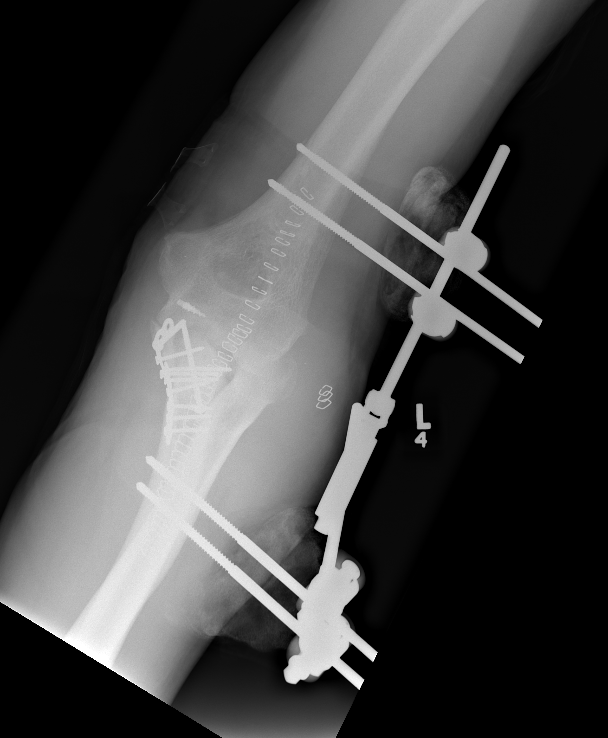

External fixator elbow 1External Fixator Elbow 2

elb ex fixelb ex fix

Compass Hinge Lateral XrayCompass Hinge AP Xray